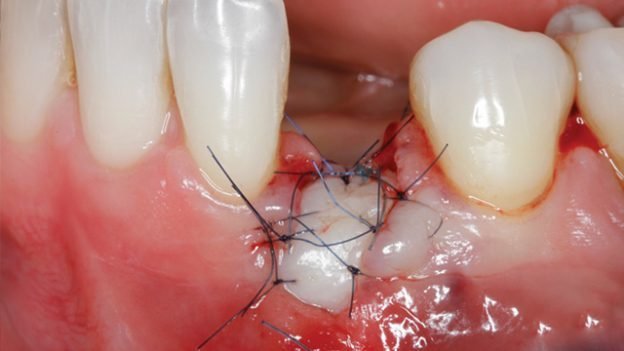

The pioneers and clinical experts in the field of soft tissue management around natural teeth and dental implants will answer all questions you have involving diagnosing mucogingival problems, thin versus thick biotype, palatal strip grafts versus connective tissue grafts versus soft tissue substitutes, split-thickness versus full thickness flaps and suturing techniques and materials.

In this live and recorded web-based Master Class, we will also cover periodontal principles for root coverage and increase of keratinization, implant site development with soft tissue grafts and substitutes, treatment of soft tissue complications and deficiencies and patient management before and after surgical soft tissue procedures.

- CLINICAL VIDEO Tunneling Procedure & Connective Tissue Grafting | Dr Francesco Mintrone